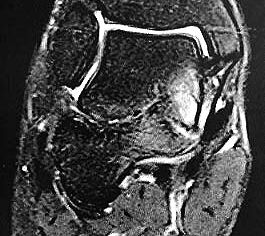

Z.n. Distorsion des Fußes mit „Ruptur“ der (vorbestehenden) talocalcanearen Coalitio. Die Wassereinlagerung in den an die Coalitio angrenzenden knöchernen Bezirken ist im MRT gut zu erkennen. Nach monatelangen Beschwerden spontane Besserung.

Abbildung 1

Die zweite wichtige Form tarsaler Coalitiones findet sich im medialen Bereich des Subtalargelenkes, am häufigsten unter Einbeziehung der medialen, mittleren Facette des talocalcanearen Gelenkes (Abb. 9). Die Ausdehnung der zunächst fibrösen, später zunehmend verknöcherten Brückenbildung kann sehr unterschiedlich Anteile der hinteren Kammer des unteren Sprunggelenkes mitumfassen; auch rein dorsomediale Formen ohne Einbeziehung der medialen Facette werden beobachtet (Abb. 2) 67 (Hamel 2008).

Diagnostisch sollte neben Röntgenübersichtsaufnahmen (indirekte radiologische Zeichen: Dorsaler Traktions-Osteophyt am Taluskopf, „talar beaking“; kontinuierliche Linie der Trochlea-tali-Kontur übergehend in die Sustentaculum-tali-Kontur, „C-Zeichen“ (Abb. 11) 10) immer die dreidimensionale Bildgebung eingesetzt werden. Das MRT (mit Kontrastmittel) kann die Struktur der Brückenbildung und z.B. die Qualität des Restgelenkes (Knorpel-Dicke) besonders gut abbilden; das Dünnschicht-CT zeigt die knöcherne Feinstruktur im Bereich der Coalitio und den oft sehr schrägen Spalt-Verlauf im Frontalschnitt dagegen häufig genauer. Meist findet sich die Überbrückung im Bereich der medialen Facette; die Schichten sollten jedoch bis weit nach dorsal beurteilt werden, da ansonsten dorsomediale Formen übersehen werden können. Rozansky et al 7 unterschieden fünf morphologische Typen auf der Basis von 3-D-CT-Rekonstruktionen. Allerdings ist eine prognostische Zuordnung bisher nicht möglich.